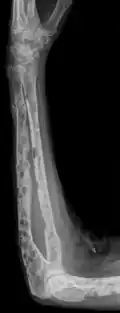

The diagnostic examination of a person with suspected multiple myeloma typically includes a skeletal survey. This is a series of X-rays of the skull, axial skeleton, and proximal long bones. Myeloma activity sometimes appears as "lytic lesions" (with local disappearance of normal bone due to resorption) or as "punched-out lesions" on the skull X-ray ("raindrop skull"). Lesions may also be sclerotic, which is seen as radiodense.[76] Overall, the radiodensity of myeloma is between −30 and 120 Hounsfield units (HU).[77] Magnetic resonance imaging is more sensitive than simple X-rays in the detection of lytic lesions. An MRI may supersede a skeletal survey, especially when vertebral disease is suspected. Occasionally, a CT scan is performed to measure the size of soft-tissue plasmacytomas. Nuclear Medicine Bone scans are typically not of any additional value in the workup of people with myeloma (no new bone formation; lytic lesions not well visualized on nuclear bone scan).

X-ray of the forearm, with lytic lesions -